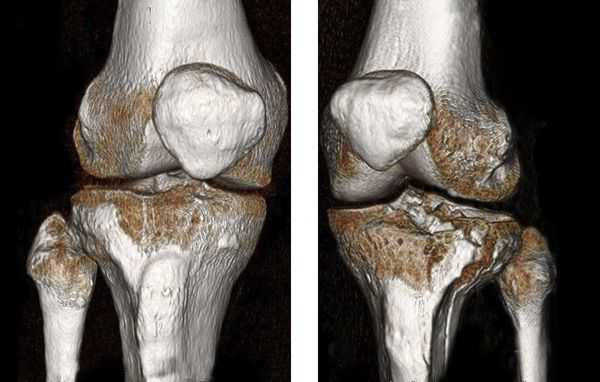

КТ коленного сустава и голени. Оскольчатый перелом большеберцовой кости в верхней трети диафиза (красная стрелка), перелом головки малоберцовой кости (синяя стрелка), перелом латерального мыщелка большеберцовой кости (зеленая стрелка).